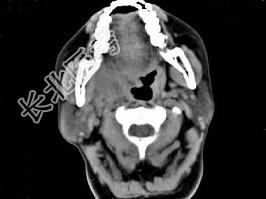

- 单项选择题女,52岁, 咽喉部疼痛半个月,伴低热, CT如图所示,最可能的诊断是 ( )

A、咽旁脓肿

B、咽部神经鞘瘤

C、鼻咽纤维血管瘤

D、咽旁淋巴瘤

E、咽旁转移瘤